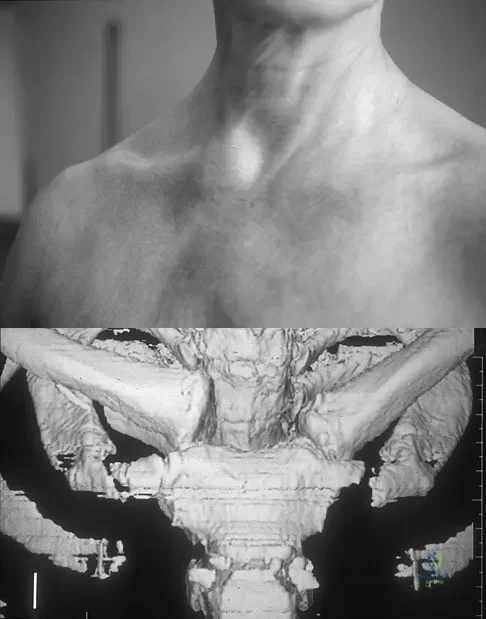

Figure 11a shows the clinical photograph of a 46-year old woman who reports a 3-week history of pain and a "lump" at the base of her neck. She is otherwise in good health and denies any trauma. A 3-D reconstruction CT is shown in Figure 11b. What is the most likely diagnosis?

Explanation